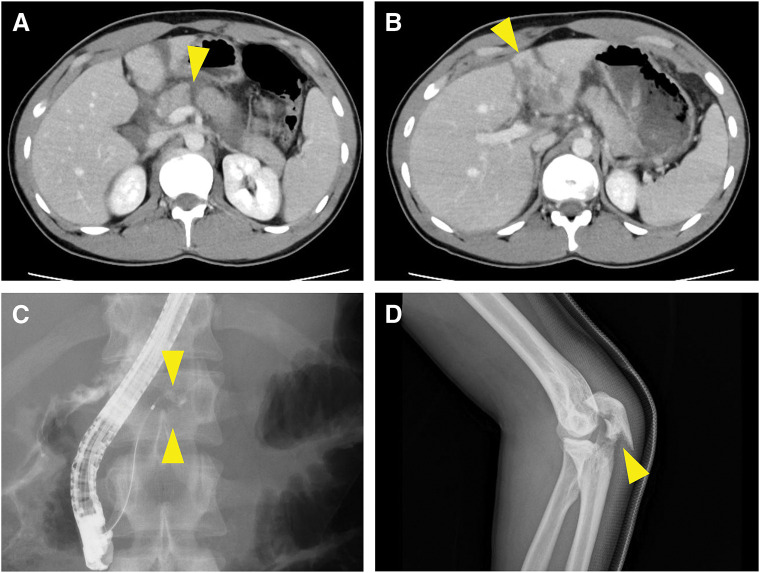

Case presentation: We report 2 cases of young patients with MPD injuries from blunt trauma, both presenting late with significant peripancreatic contamination. Case 1 included a 22-year-old male who sustained pancreatic and liver injuries while skiing. He was transferred 30 hours post-injury with stable hemodynamics. Endoscopic retrograde pancreatography (ERP) confirmed MPD disruption. Intraoperatively, saponification obscured the anatomical structures, but MP with PJ was successfully performed. The patient recovered without major complications. Case 2 involved a 17-year-old female who was initially observed at another hospital after a traffic accident. Three days later, she developed peritonitis, and a retrospective computed tomography review revealed a pancreatic body rupture. An ERP confirmed MPD disruption. During surgery, extensive inflammation and adhesions were noted, and the MPD was extremely small. Despite technical complexities, an MP with PJ was successfully completed. The pancreatic fistula from the pancreatic head stump required drainage treatment following spinal surgery for vertebral fractures, and the patient recovered without sequelae.